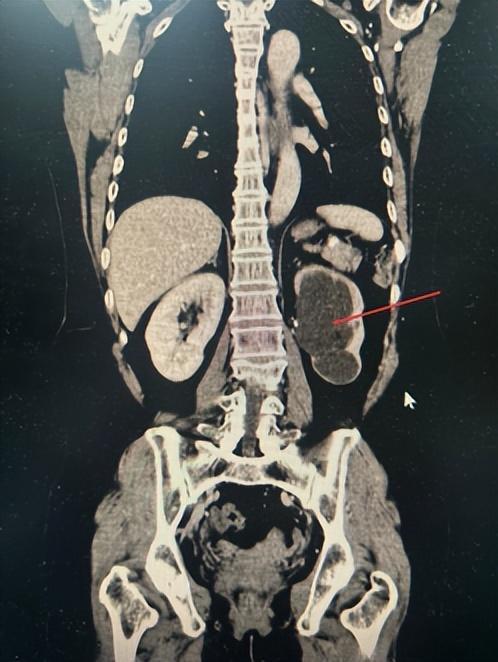

近日,一位反复腰痛的中年女性患者,因既往有多次输尿管结石手术史,怀疑自己再次输尿管结石发作,来湖南省中西医结合医院(湖南省中医药研究院附属医院)泌尿外科门诊就诊。

医生为其完善检查后,发现不是结石,而是肾脏重度积水,结合患者病史及辅助检查,被确诊为输尿管狭窄合并重度肾积水。完善输尿管镜检,并予以扩张、输尿管支架置入后,肾积水基本消失,但患侧肾脏功能已受到明显损伤。

(▲输尿管狭窄合并重度肾积水)